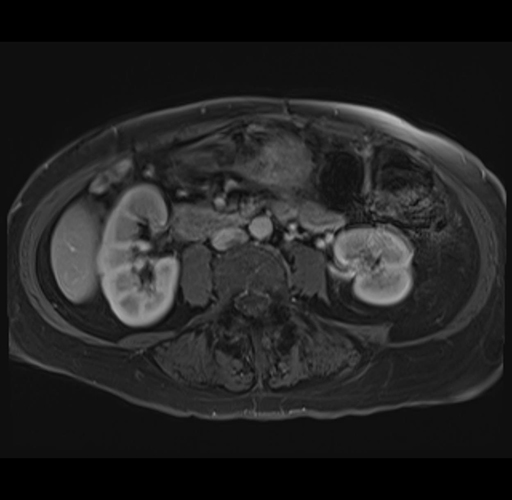

MRI T1